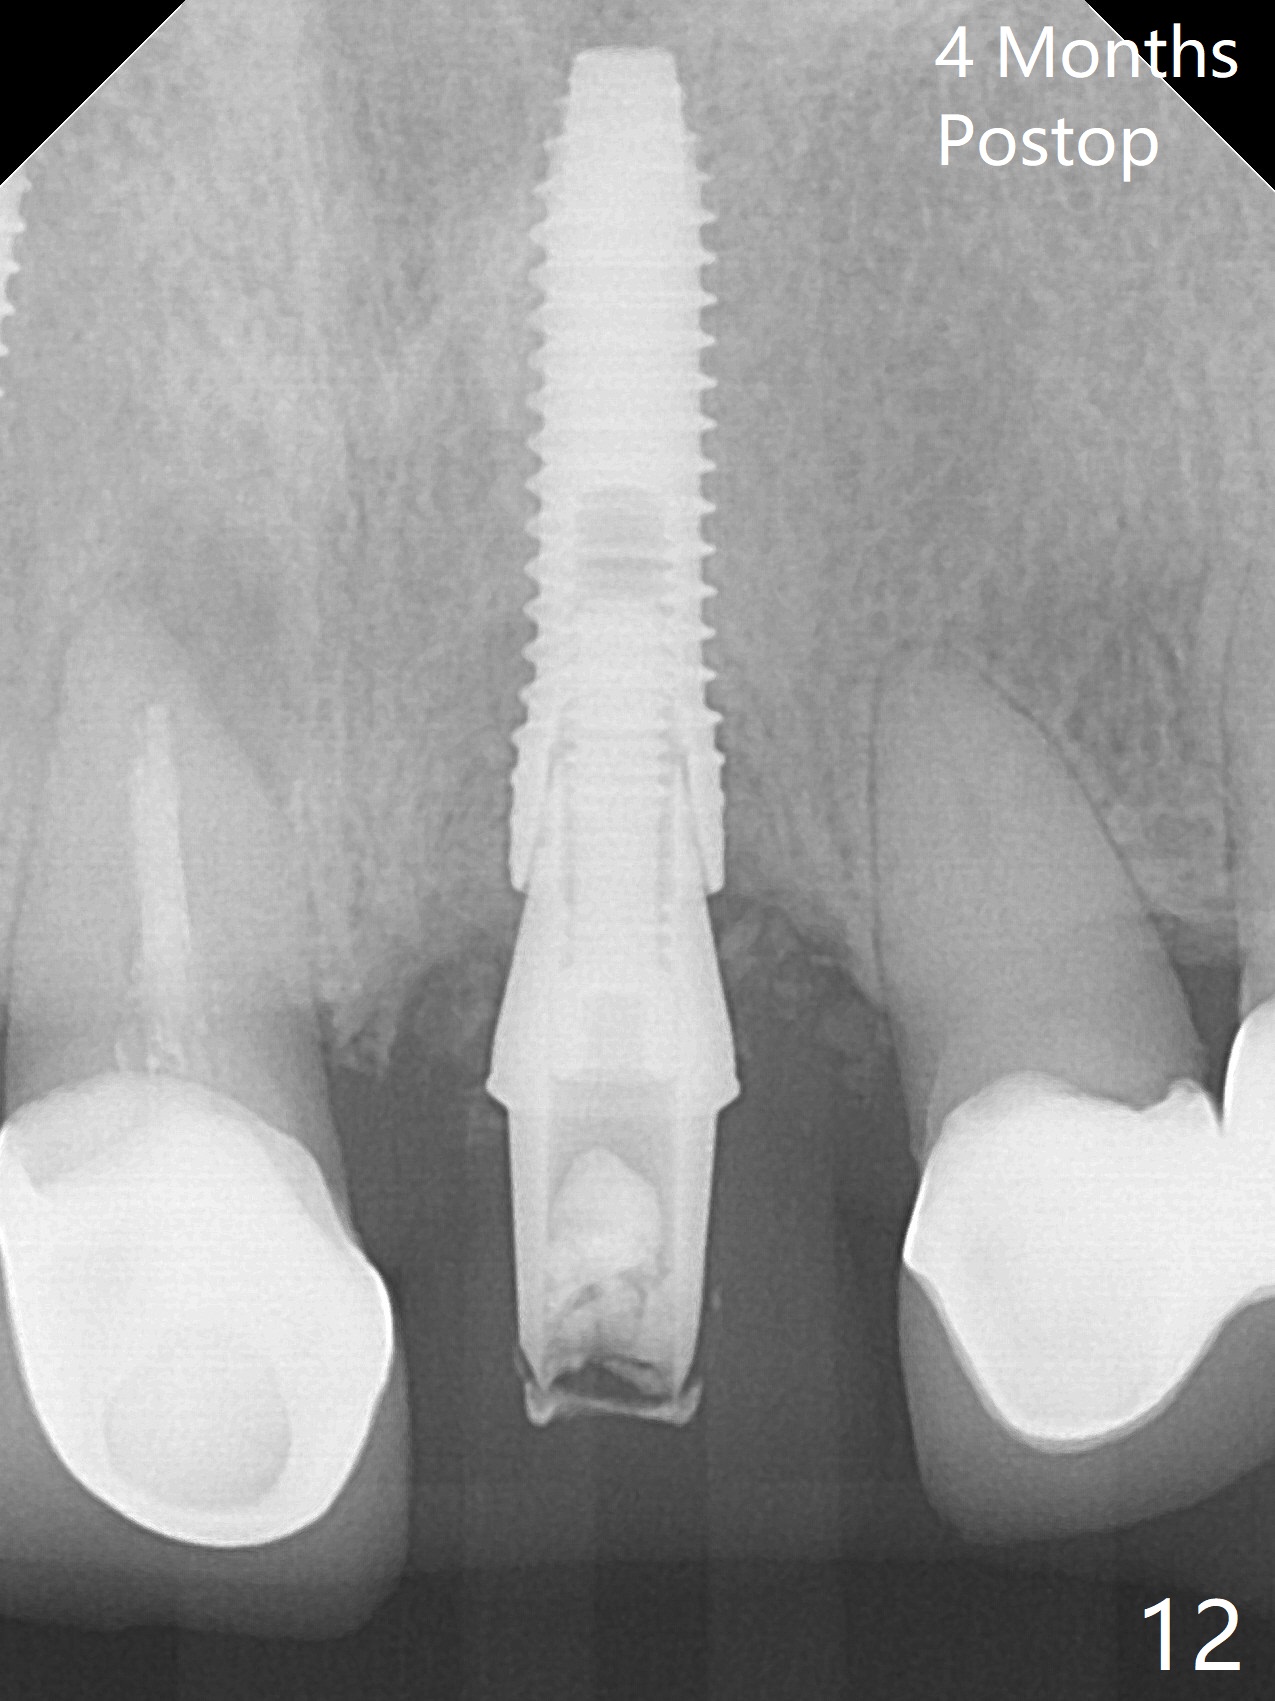

Nasal Floor

The buccal contour at #9 seems to be slightly concave preop (Fig.1,2 (*)). In fact the buccal plate is found to be lost when the tooth is extracted. Osteotomy is initiated as palatal as possible apical, but the occlusion dictates the coronal end of the osteotomy should be buccal, leaving the buccal gap ~ 2 mm for bone graft. The initial osteotomy (18 mm deep) appears to be close to the Incisive Foramen (Fig.3 blue dashed line). The nasal floor appears to be intact when the drill is removed. Subsequent osteotomy is adjusted so that the apical end of the osteotomy moves distal; when a 3.8x15 mm dummy implant is partially placed, there is clearance (Fig.4). It remains so when a definitive implant is seated (Fig.5); Vanilla graft is placed (Fig.5 *) before placement of a 4.5x5.5(3) mm abutment. More allograft is placed when an immediate provisional is fabricated (Fig.6 arrow and *). The gingiva remains to be recessive 1 month postop (Fig.7). It seems to be related to the bulky gingival margin of the provisional (Fig.8 *). After trimming the latter (Fig.9 *), the gingival margin immediately returns close to normal (Fig.10). The gingival margin is even between #8 and 9 two months postop, but the bone graft is exposed apically (Fig.11 ^). It may heals by itself. Otherwise debridement, regraft, PRF and suture are pending. The coronal portion of the socket heals 4 months postop (Fig.12). The gingival cuff forms by the immediate provisional (which is removed for impression) 4 months postop (Fig.13 *). While the full Zirconia crown at #7 remains intact (Fig.14), the PFM at #9 has porcelain chip (Fig.15). It is partially due to the occlusion; while the crown at #7 has clearance with the opposing dentition (Fig.16 *), the one at #9 has no. The access hole at #9 (Fig.17 *) seems to weaken the crown structure. There is no access hole at #7. No solid posterior support is another contributing factor for chip (Fig.18). The buccal plate has mild atrophy at #7 and 9 (Fig.19 *). A piece of bone graft is being expelled apically at #9 (Fig.20 >) and is removed subsequently (Fig.21). Before impression for repacking porcelain, the opposing incisal edge has been shortened (Fig.22 arrows, as compared to Fig.16). Since the ideal access hole is at the incisal edge (Fig.25 black circle), buccal to the existing one (Fig.24 A), the abutment is torqued before the repaired crown is recemented (Fig.23). Finally the crown has occlusal clearance (Fig.26). Porcelain chips again around the access hole of PFM 1.5 years post 2nd cementation. The dense bone at the crest (*) cannot explain why the abutment is not loose, since it remains incompletely seated (>). As it was trimmed short, an angled abutment is used (Fig.28). The coronal end is lingual, while #9/24 is edge to edge. The lingual aspect of the coronal end of the abutment is heavily trimmed to reduce bulkiness. To prevent chip, Zirconium crown will be fabricated in spite of the fact that it does not match the PFM of #8 (potential shade discrepancy). The patient is pleased with the new Zirconia crown (Fig.29).